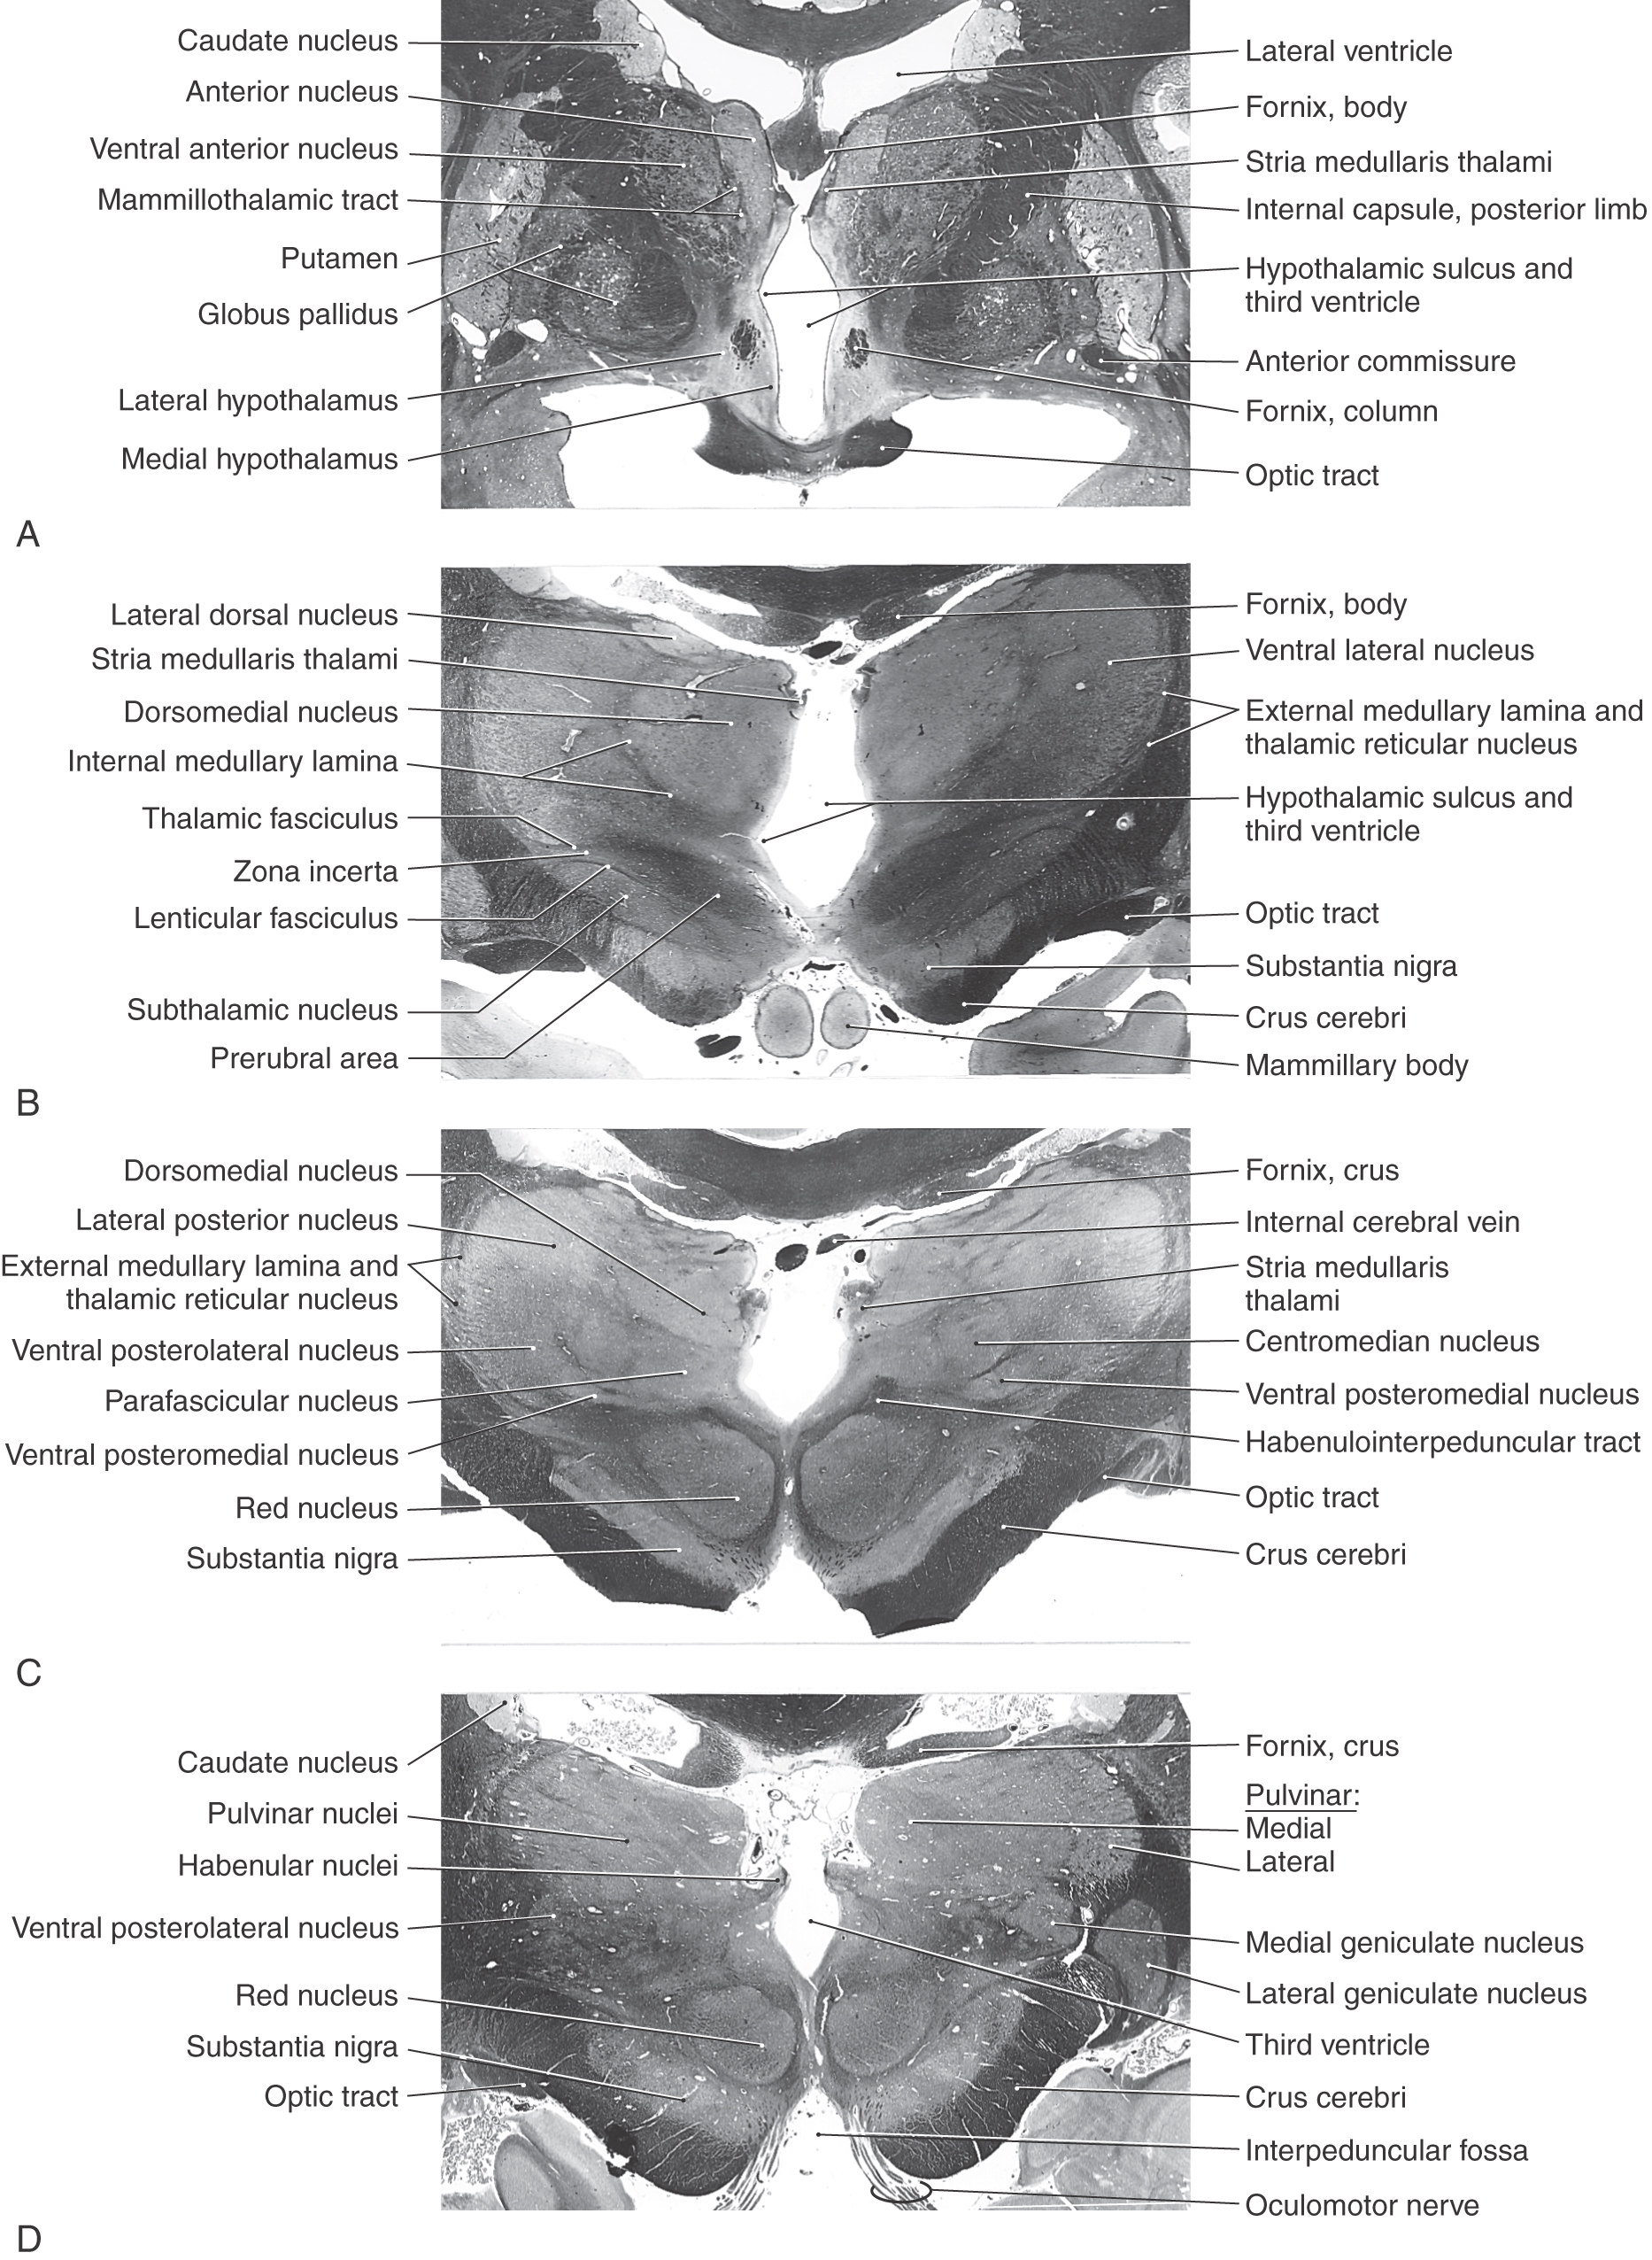

Figure 15-6. Midsagittal view of the diencephalon. This view correlates with the drawing in Figure 15-3. Lines A through D indicate the planes of the stained sections in Figure 15-7.

image

Figure 15-7. Four levels of the forebrain from rostral (A) to caudal (D) showing the internal structure of the hemisphere with emphasis on the diencephalon. These levels correlate with those shown in Figure 15-6 and with the planes represented in the exploded view in Figure 15-10. Weil stain.

All four diencephalic subdivisions can be approximated in a midsagittal section of the forebrain (Figs. 15-4 and 15-6). The dorsal thalamus is located superior to the hypothalamic sulcus and extends from the interventricular foramen caudally to the level of the splenium of the corpus callosum. The hypothalamus lies inferior to the hypothalamic sulcus and is bordered rostrally by the lamina terminalis and caudally by a line that extends from the posterior aspect of the mammillary body superiorly to intersect with the hypothalamic sulcus. The only diencephalic structures visible on the inferior surface of the hemisphere are those related to the hypothalamus, including the optic chiasm, infundibulum, medial and lateral eminences, and mammillary bodies (Fig. 15-5). The ventral thalamus (subthalamus) does not border on the ventricle; rather, it occupies a position caudal to the hypothalamus, rostral to the diencephalon-midbrain junction, and lateral to the midline (Figs. 15-4 and 15-7B). Epithalamic structures are located posteriorly and caudally, in close apposition to the posterior commissure, and include the pineal gland, the habenular nuclei, and the main afferent bundle of these nuclei, the stria medullaris thalami.